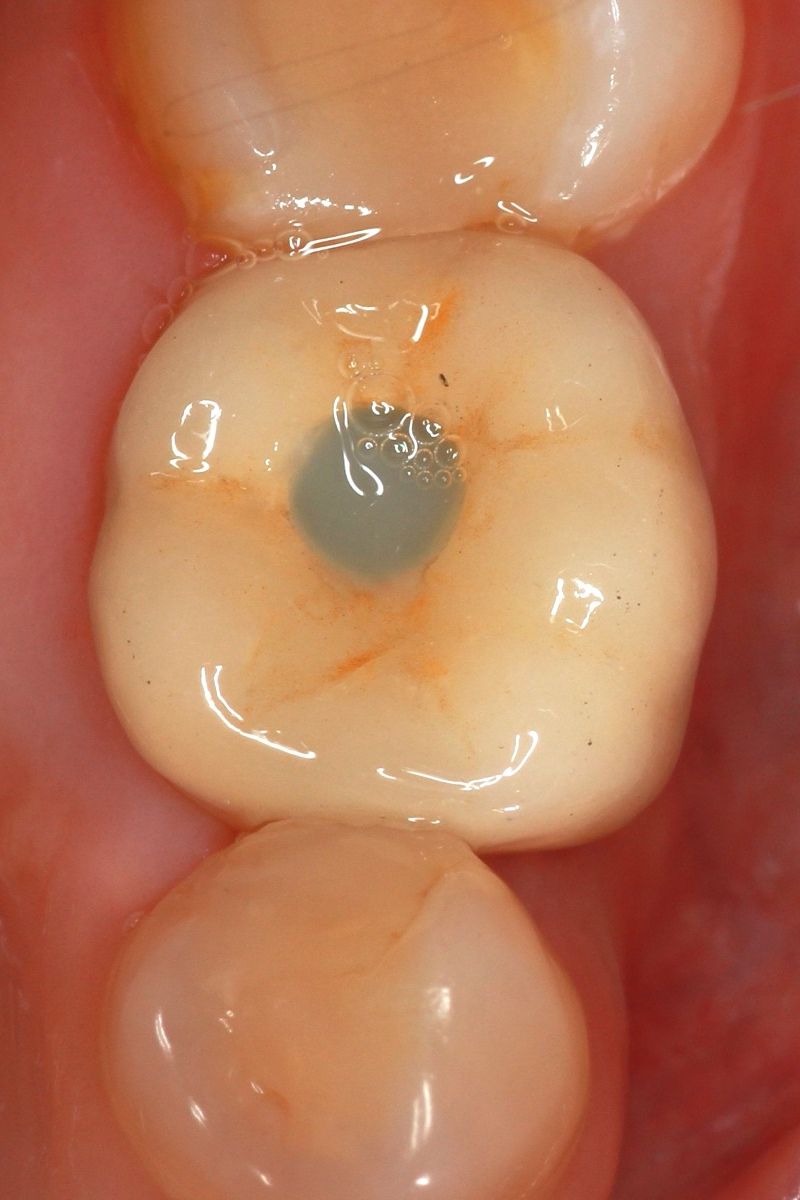

Installing the crown

We install an individual abutment, fix the crown